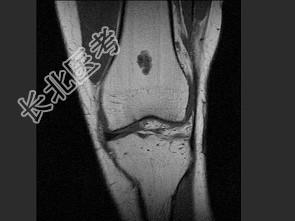

- 单项选择题女,21岁, 右膝部感不适,结合图像, 最可能的诊断是 ( )

A、股骨骨囊肿

B、股骨内生软骨瘤

C、股骨巨细胞瘤

D、股骨血管瘤

E、股骨结核